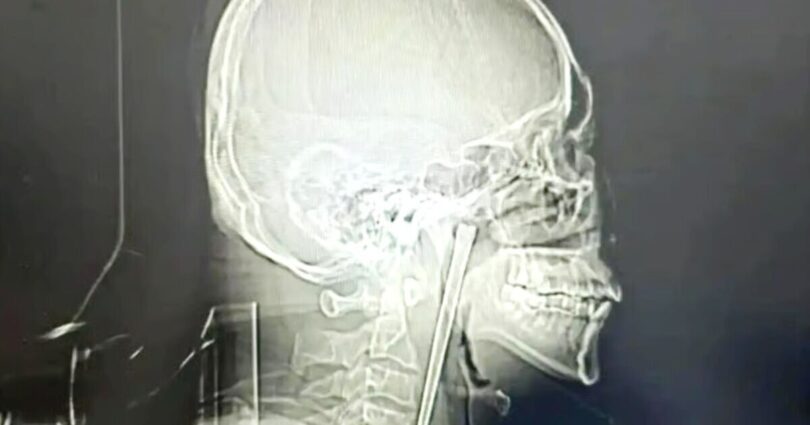

This is the incredible X-ray of a man in China showing a 12cm-long chopstick he had stuck in his throat for an astounding eight years, because he was terrified of surgery. The man, who it’s reported had the surname Wang, only eventually went to hospital in March after finally having enough of the oesophageal interloper.

Eventually however Mr Wang decided to undergo surgery and had the chopstick removed at Dalian Municipal Central Hospital in northeastern Liaoning province in early March. X-rays of the chopstick show how he endured having the huge eating implement lodged in his neck for nearly a decade.

An examination found the metal chopstick has embedded in the soft tissue around Mr Wang’s throat, but incredibly it had not damaged his food or breathing tubes, or his vocal cords.